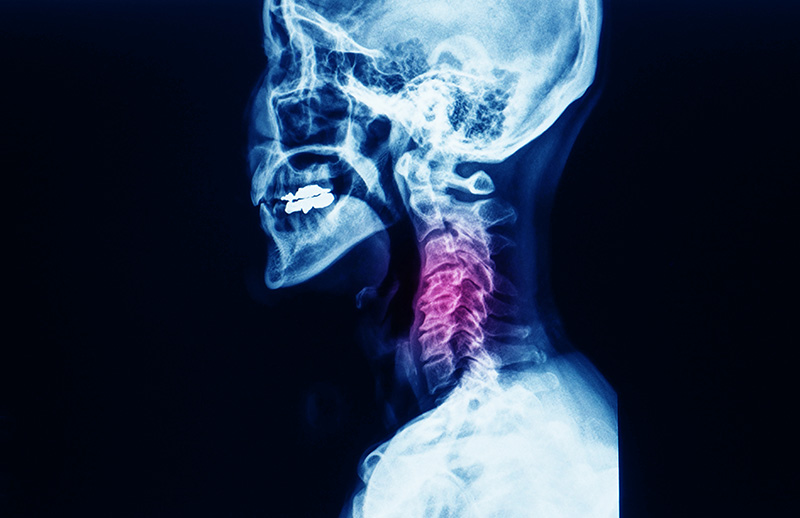

Servikal Stenoz Ameliyatı

Anterior Servikal Diskektomi

Servikal Foraminotomi